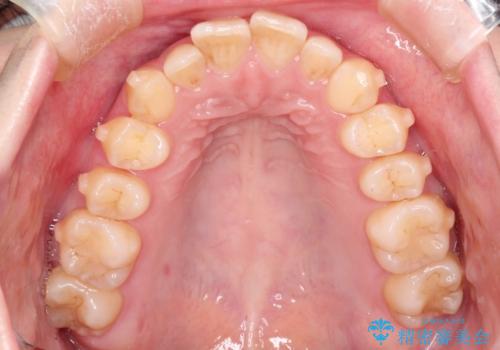

出ている前歯をインビザラインにて引っ込める

- 前歯が少し前に出ているのが気になるとのことで来院されました。

インビザラインにて上顎の歯を全体的に後方に移動させて前歯を引っ込める計画としました。